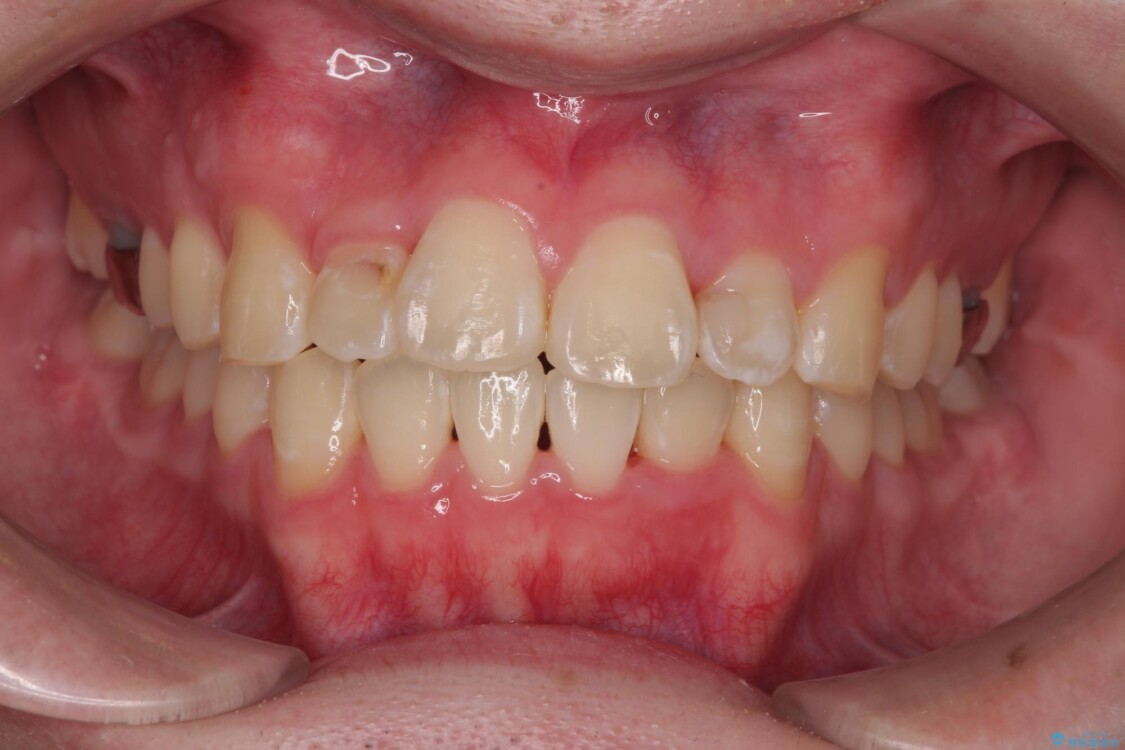

「歯並びがデコボコしていて、上下の中心がズレているのが気になる…」という悩みで来院された患者さまの症例をご紹介します。

初診時の状態

・上下ともに歯がきれいに並びきらず、がたつきが見られました。

・上下の前歯の中心(正中)がずれています。

・特に上顎の幅が狭いため、下顎の歯列も内側に入り込み、歯が並ぶスペースが不足していました。

治療前